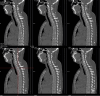

Tuberous sclerosis complex (TSC) is an autosomal dominant genetic disorder characterized by the development of benign tumors and lesions in multiple organ systems. The syndrome arises from heterozygous mutations in either TSC1 or TSC2. In this study, we identified a family with a TSC1 c.363 + 668G > C mutation exhibiting diverse clinical phenotypes. The proband and affected family members exhibited multifocal nodular pneumocyte hyperplasia (MMPH), renal hamartomas, bone marrow hyperplasia, and pulmonary lymphangioleiomyomatosis (LAM), with genetic co-segregation analysis confirming the association between the mutation and the clinical phenotype. Genetic co-segregation analysis demonstrated that the TSC1 c.363 + 668G > C mutation was consistently associated with the observed clinical features in this family. Using first-generation Sanger sequencing, we identified a heterozygous splicing variation located in intron 5 of TSC1 (NM_000368.5). In vitro cell and family Minigene results show that TSC1 c.363 + 668G > C mutation can lead to abnormal retention of 92 bp intron sequence in different positions, which may be related to the alternative splicing phenomenon that the same gene produces different splicing variants in different tissues or development stages. The 3D protein structure analysis using Chimera revealed that the mutation site was located at the 363rd base, within the intron between the 121st and 122nd amino acids. This mutation resulted in the insertion of a 92-base sequence, causing a frameshift that led to premature termination of the TSC1 protein after the translation of 26 amino acids. Additionally, the 121st amino acid was altered from lysine to asparagine, significantly shortening the mutated TSC1 protein. These findings provide critical experimental evidence supporting the potential pathogenic mechanism of the TSC1 c.363 + 668G > C mutation. Future research should focus on validating this splicing abnormality in patient-derived cells or tissues and investigating its impact on protein expression and functional activity to better understand its role in disease progression.Clinical trial number: K2024-09-144.